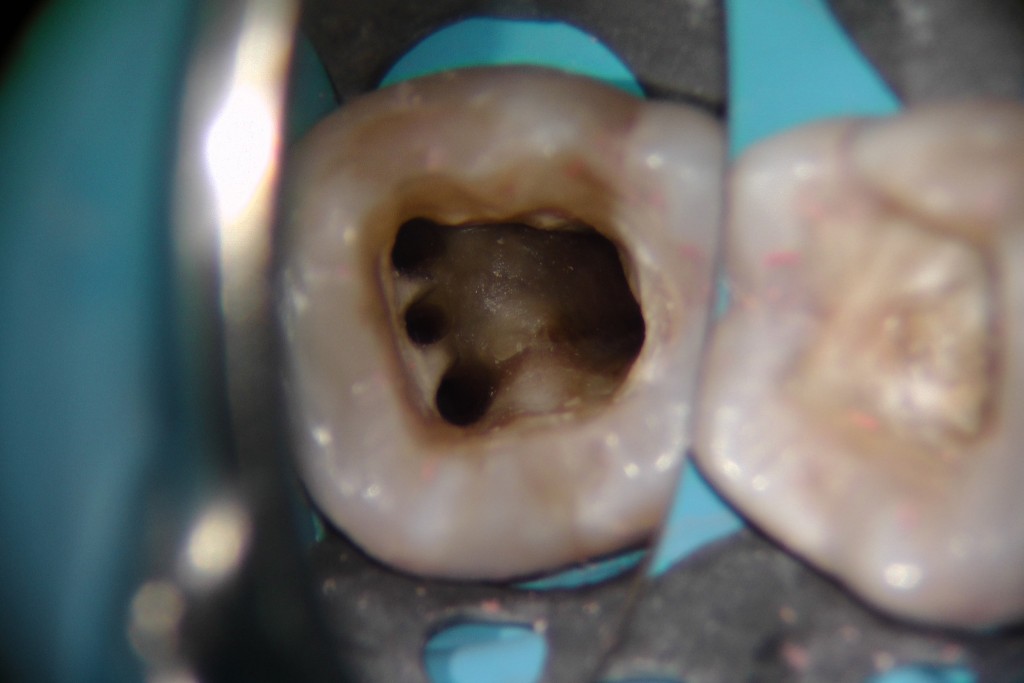

Ora ti mostro qua sotto come reperire il canale mesiale-mediano.

E come facevano? Si approfondivano di 2 mm nell’istmo tra i canali mesio-vestibolare e mesio-linguale con un fresina diamantata larga 1 mm in punta. Così facendo aumentavano il reperimento complessivo da 6 casi (tutti primi molari) a 42, di cui 21 secondi molari!

Di solito, essendo l’Mtwo viola uno strumento fenomenale per reperire e sondare in un sol colpo i canali stretti o calcificati, dopo aver sagomato i canali MV e ML provo a inserire questo strumento più volte nell’istmo tra i due canali suddetti. Se non sento un impegno allora mi approfondisco di 2 mm tra i canali MV e ML con una StartX 3 o , più spesso, con una fresina diamantata larga 0,8 in punta e il gioco è fatto.